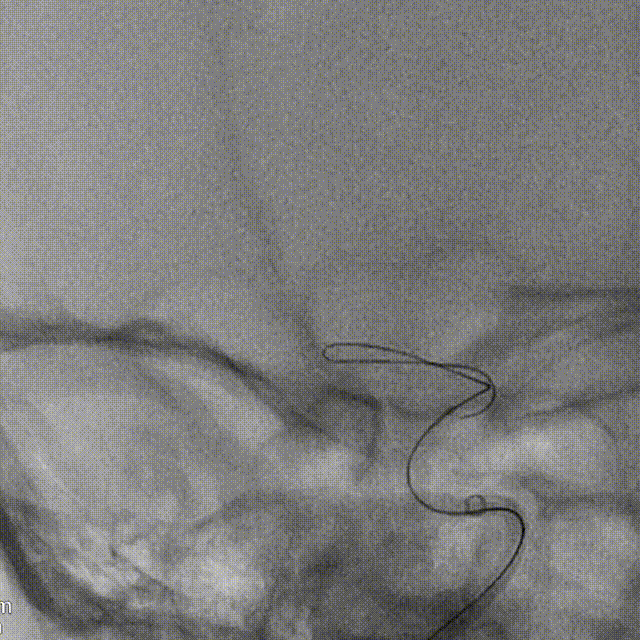

支架到位,原位释放,前段打开。

造影确认支架远端打开充分,贴壁良好,继续推送支架。

支架全部释放,调整张力,微导管通过支架,回收输送导丝。

支架内使用成襻微导丝进行按摩,使支架充分贴壁。